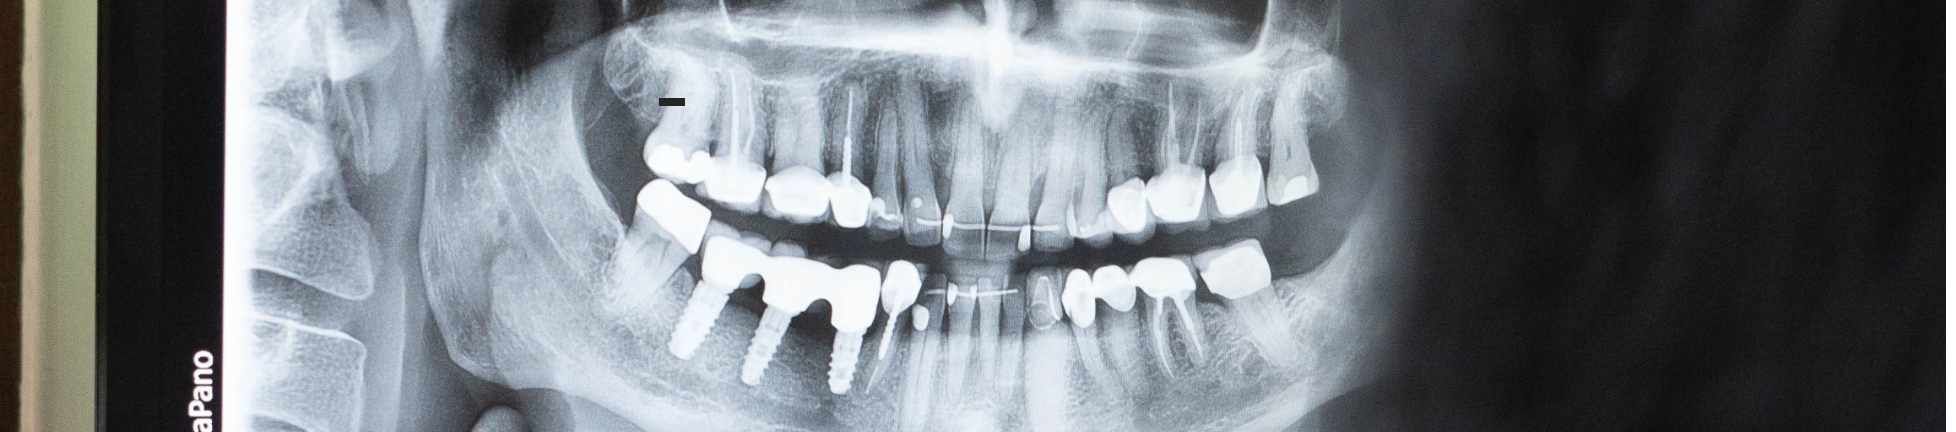

Implanty to nowoczesne rozwiązanie w stomatologii, które umożliwia trwałe uzupełnienie braków zębowych. Są to niewielkie, najczęściej tytanowe śruby, które chirurgicznie wszczepia się w kość szczęki lub żuchwy w miejsce utraconego zęba. Implant pełni funkcję korzenia zęba, a na jego podstawie osadza się koronę protetyczną, która do złudzenia przypomina naturalny ząb – zarówno pod względem estetyki, jak i funkcji.

Konsultacja i diagnostyka – Oceniamy stan jamy ustnej i wykonujemy badania, np. tomografię 3D.

W naszej placówce często stosujemy implantację nawigowaną, ponieważ umożliwia ona precyzyjne spozycjonowanie implantu zgodnie z planem leczenia, co zwiększa przewidywalność i skuteczność terapii.

Technika ta jest szczególnie przydatna w strefie estetycznej, przy rozległych rekonstrukcjach z natychmiastowym obciążeniem oraz w przypadkach, gdy dostępna przestrzeń na implant jest znacznie ograniczona.